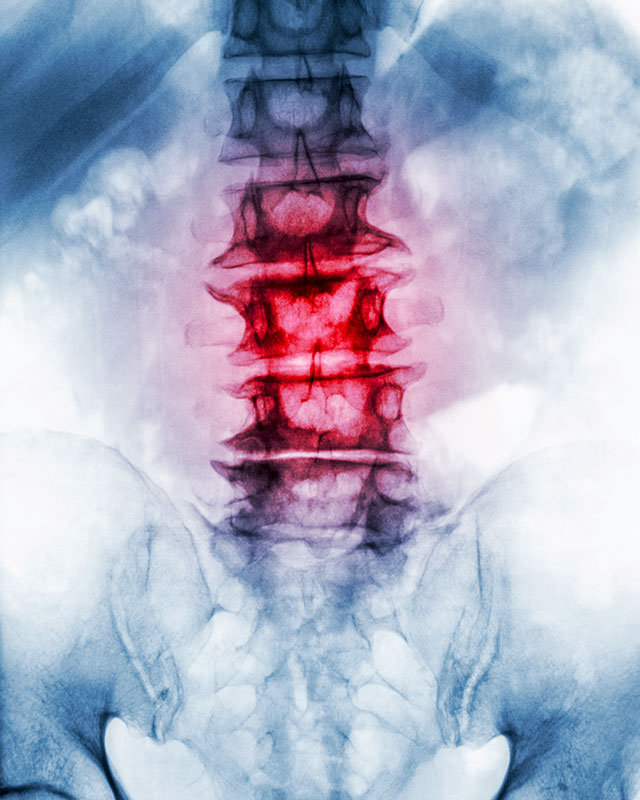

Chiropractic is a health profession that focuses on the spine and other joints of the body and their connection to the nervous system. It’s based on the premise that good health depends substantially upon a normally functioning nervous system. Body parts, organs and cells function mostly under the control of nerve impulses to and from the brain and spinal cord.

When there is interference to this normal transmission, normal function is interfered with, and malfunction may result, predisposing a part of your body to pain or other disorder. In chiropractic this is called joint dysfunction or vertebral subluxation. Effects of joint dysfunction ›

The spinal cord leads to 31 pairs of spinal nerve roots that exit the spinal bones. Although the spine offers support and protection for the delicate and sensitive spinal cord and the nerve roots, it can also cause nerve interference when the spinal joints are jammed. You get a ‘pinched’ or ‘trapped’ nerve.